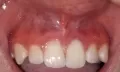

Двенадцать дней назад делала передние верхние зубы (был кариес), мне поставили светопломбы. Три дня назад проснулась с опухшей верхней губой, отек спал довольно быстро. Но со вчерашнего дня у меня над десной в районе носа шишка, болит, даже больно улыбаться, части носа тоже больно, нажимать больно, отдает в зуб. Но когда стучишь по зубам — не больно.

По Вашим симптомам можно сказать, что у вас обострение хронического воспаления (периодонтит). Причина, как правило, некачественное эндодонтическое лечение. Обратитесь срочно к стоматологу-терапевту, в противном случае Вы можете серьёзно повредить и даже потерять зуб